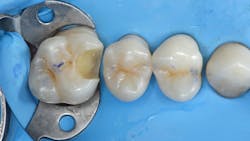

In addition to optimal bonding, the rubber dam may retract the tissues when placed properly, improving our visualization of finish lines, margins, and adhesive materials. One of dentistry’s rubber dam advocates, Dr. Hunter Brinker (the inventor of the B1-B6 clamps), often said “to see is to know” when referring to the benefits of the rubber dam to improve attention to detail through better visual access. It is interesting to note that when the rubber dam is properly placed, it will not only retract the tongue, lips, and cheeks, but it will also atraumatically retract the gingiva, typically 2–3 mm, and expose areas that could not be visualized by any other nonsurgical means (figures 3–5).

With an inverted rubber dam, however, bleeding becomes a nonissue and allows the clinician to focus on preparation design, pulpal protection, adhesive strategies, and restoration placement—all in a clean and well-sealed environment.3 “Beating the blood” need not be your approach when one of dentistry’s least-used gems is close at hand (figures 6 and 7).

Inverting (no need to ligate teeth with floss)

The most important step to ensure a moisture-free dam that is well sealed and can retract the tissue is inverting the rubber dam. This step is performed after the dam has been flossed through the contacts and rinsed and dried. An explorer with air spray usually inverts most areas. When checking for inversion, floss the interproximals and hug the tooth while doing so; this will usually flip the dam over without inverting the explorer further.